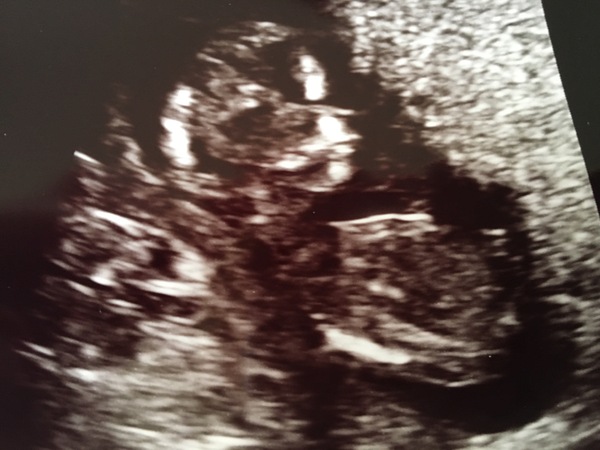

Thank you music! We're very happy and excited to be expecting a pink one 💗 unfortunately she was very snuggled up to the placenta so no useable 3D shots but here she is at 16 weeks!

Congratulations MrsG! Great pic x

Amazing - congrats mrs g!

Aaaah a little girl! Congratulations mrsg

Congrats Mrs 💖 Lovely scan pic

We didn't have a preference by both hubby and I had started to get a gut feeling she was a girl! Just need to keep it a secret now from family until Sunday's gender reveal party Grin my mum and dad are both convinced its a boy so they'll be surprised!

Thank you music and congrats mrsG what a lovely scan pic!